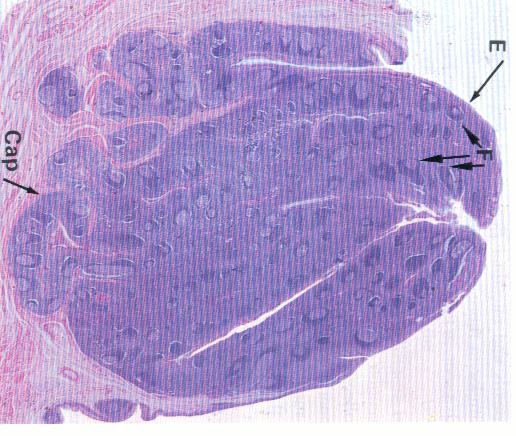

- Capsule

- Afferent → Subscapular sinus → Trabecular sinuses → Medullary sinuses → Efferent

GC: Germinal center (產生抗體, B cell)

MnZ: Mantle zone(T cell)

粉紅色: Reticular cell